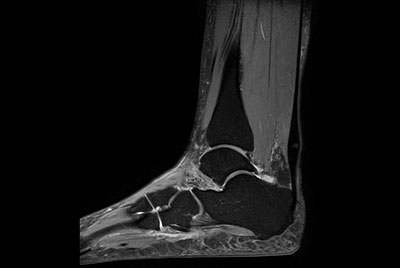

High resolution Ankle imaging in short scan times

Ankle imaging with the dS 16ch FootAnkle coil

Imaging with the dS 16ch FootAnkle coil

Ankle with Compressed SENSE

Foot and Ankle imaging

Comprehensive ankle exam in 8 minutes